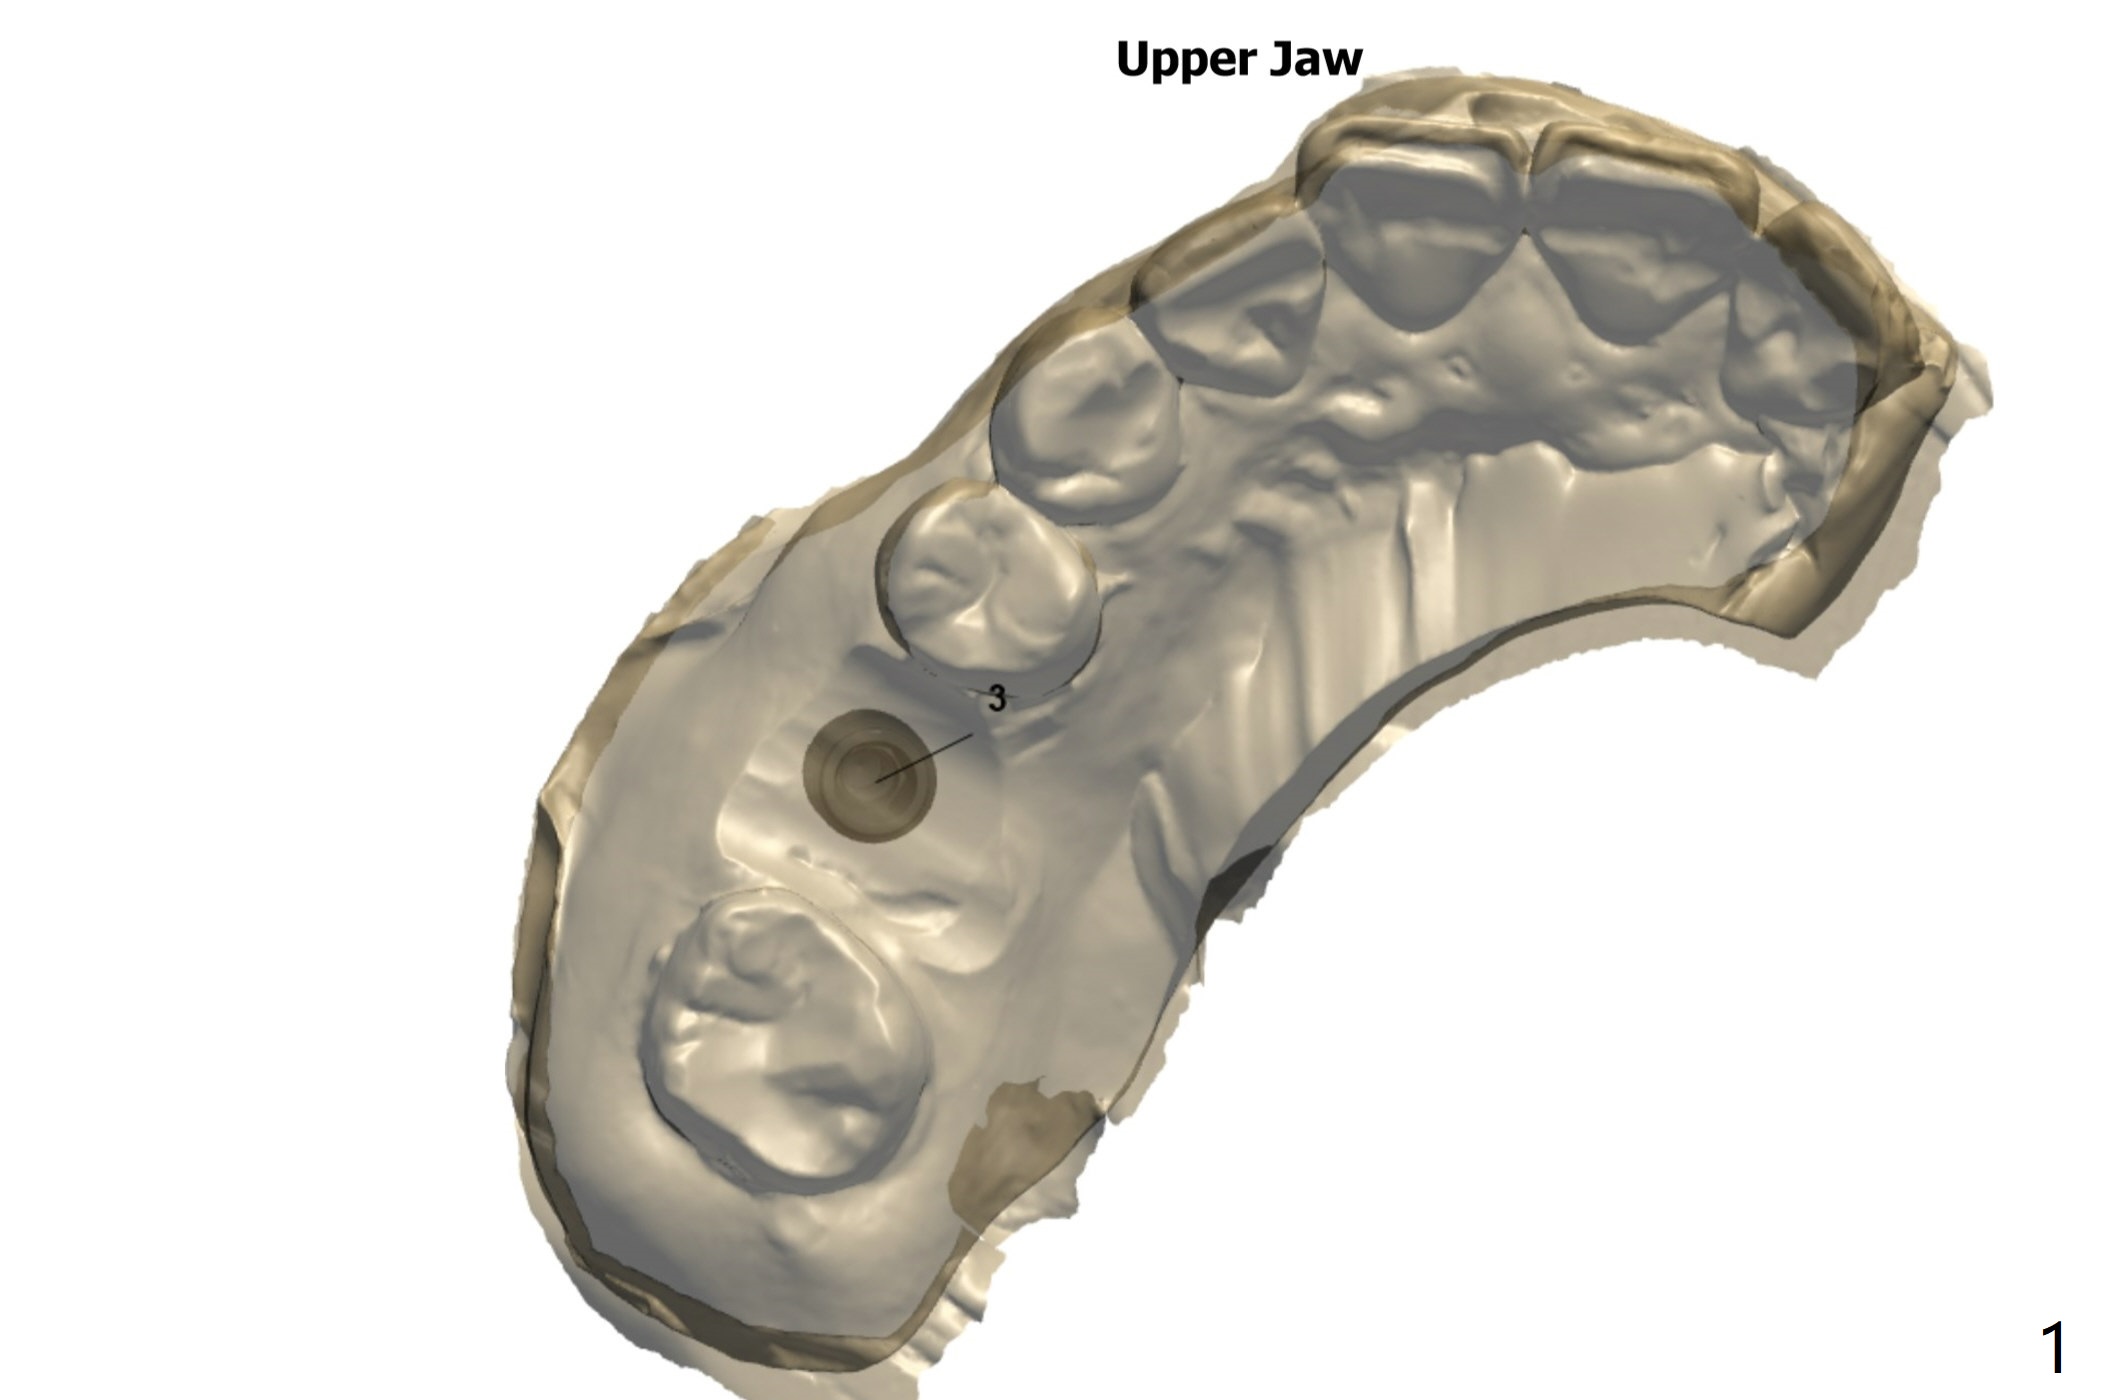

Internal Sinus Lift   M

Return to Upper Molar Immediate Implant, Prevent Molar Periimplantitis (Protocols, Table), Trajectory II, No Antibiotic